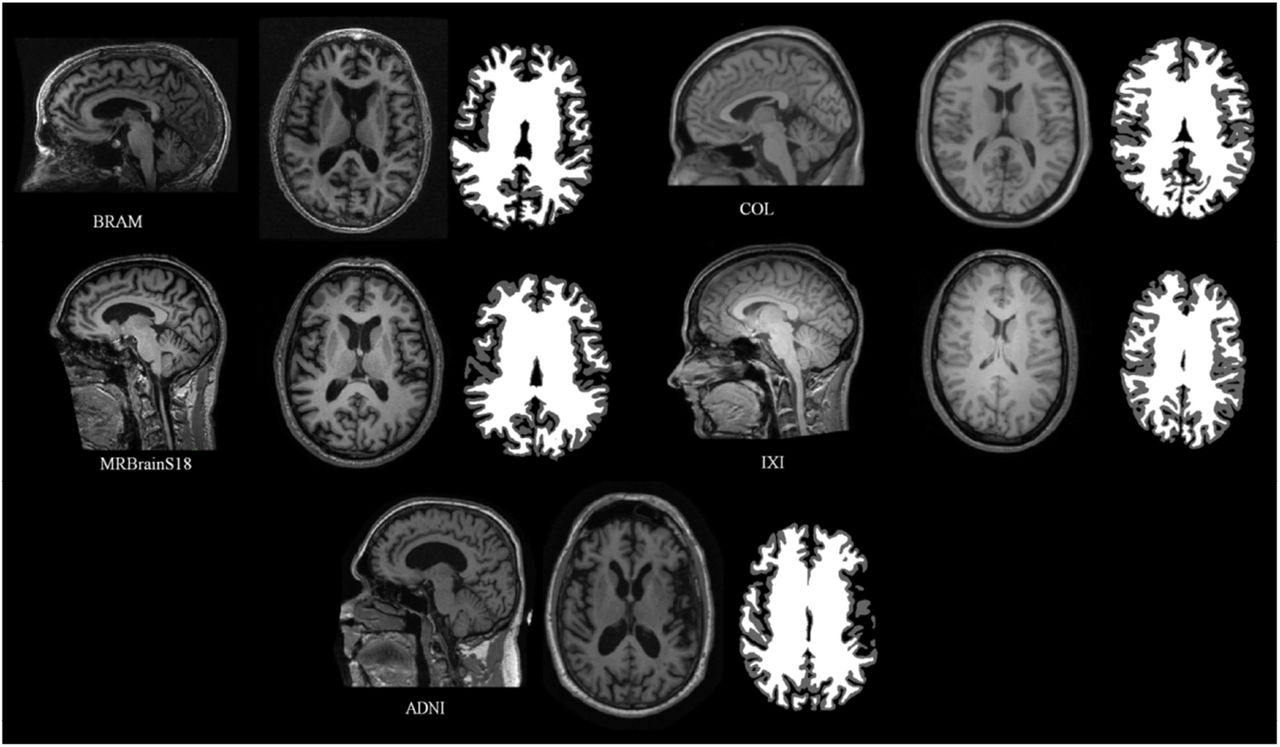

Automatic Segmentation is a hard problem!

so much variability across subjects!

Manual Segmentation or Expert Segmentation is the "Groundtruth"

extremely time-consuming

2 Experts worked on this for 6 months